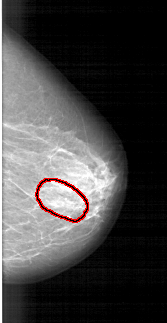

A_1390_1.RIGHT_CC

RIGHT_CC LINES 5491 PIXELS_PER_LINE 2836 BITS_PER_PIXEL 12 RESOLUTION 43.5 OVERLAY

FILE: A_1390_1.RIGHT_CC.OVERLAY

TOTAL_ABNORMALITIES 1

ABNORMALITY 1

LESION_TYPE CALCIFICATION TYPE PLEOMORPHIC DISTRIBUTION LINEAR

ASSESSMENT 4

SUBTLETY 3

PATHOLOGY BENIGN

TOTAL_OUTLINES 1

BOUNDARY